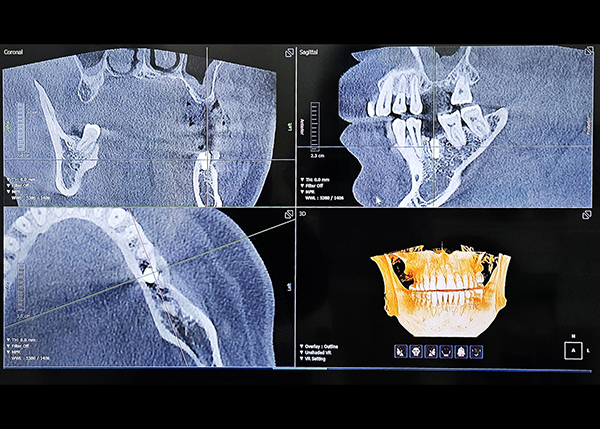

성공적인 임플란트 핵심,

대표원장의 독보적인 임상 노하우와

디지털 진료 시스템 - READ MORE

CT·CAD/CAM·3D 스캔 기반의 정밀 시스템으로

치과의사와 기공사가 만드는 1:1 맞춤 보철 - READ MORE

- Digital Optimum

- 진단부터 진료까지,

디지털 시스템 구축 - 오차를 줄인 정밀하고 완성도 높은 진단과 치료가 가능합니다